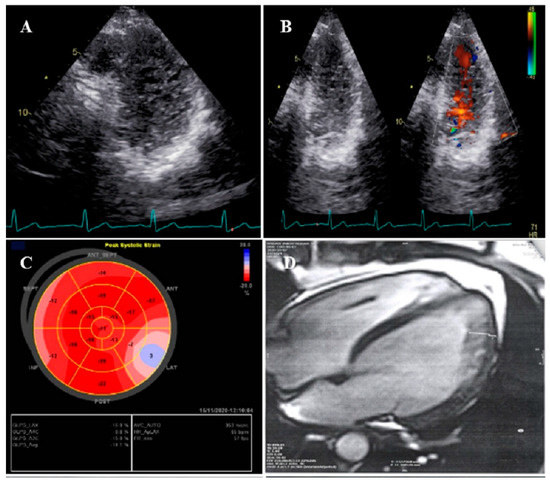

A 47-year-old gentleman who worked in the military service for 15 years was referred to our clinic with a complaint of easy fatigability and mild hypertension since 2 years ago. He was followed up with by another colleague who had the impression of mild LV systolic dysfunction and subaortic web. He received 5 mg daily amlodipine; but had mildly raised blood pressure (BP; 140/90 mmHg). When he was referred to our center, there was a discrepancy between the upper and lower extremities’ BP, and cardiac auscultation revealed a loud A2 closure sound. The review of the previously performed CXR showed posterior rib notching at three points. Computed tomography angiography of the aorta confirmed the presence of post-ductal narrowing in the descending aorta. TTE and TEE showed NCLV with mild LV systolic dysfunction (LVEF = 45%) and coarctation of the aorta with a 28 mmHg rest gradient across the coarctation site. CMR confirmed the diagnosis of NCLV (Figure 1). No other associated pathology was noted. A genetic study showed mutations in the MYH7 and MYBPC3 genes; the genetic and echocardiographic results of his siblings (one sister and two brothers) were normal. The patient was recommended to use carvedilol 6.25 mg (three times a day) and spironolactone 25 mg daily. At 1-year follow-up, the patient’s complaints had reduced and the BP was stable.

Figure 1.

The imaging results of case #1. (A); Left ventricular apical short-axis view illustrating hypertrabeculated apical portions in addition to deep intertrabecular recesses, (B); Color Doppler echocardiography, showing evidence of direct blood flow from the ventricular cavity into deep intertrabecular recesses (C); Speckle tracking echocardiographic findings, compatible with myocardial performance impairment plus relative apical sparing; GLS = −10.4%. (D); Prominent trabecular network in the apical lateral segments, (E–H); Thoracic CT angiography, showing narrowing of descending aorta, distal to left subclavian artery in different projections.